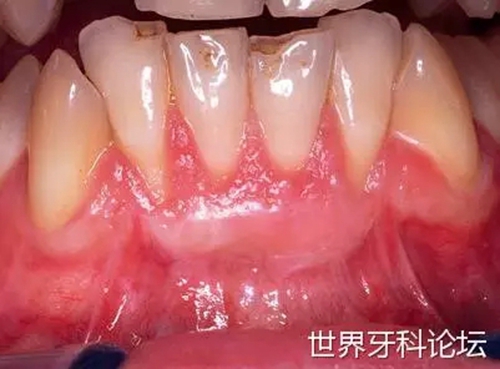

在受區(qū)翻起半厚瓣,去除所有上皮部分(圖9)。移植的牙齦組織緊密縫合于受區(qū),避免形成厚的滲出層,使最終結(jié)果受到影響(圖10)。

圖9:受區(qū)預(yù)備。

圖10:固定移植物后,激光照射位點(diǎn)。

術(shù)后 14天內(nèi),使用平頭手機(jī)以MSP模式、10Hz、0.5W(LightWalkerATS, Fotona, Ljubljana, Slovenia)、60s秒每位點(diǎn),每隔一天進(jìn)行生物調(diào)節(jié)(七次)。在術(shù)后14天(圖11)及整個(gè)42天愈合期(圖12)內(nèi),移植成功,根面得到覆蓋。